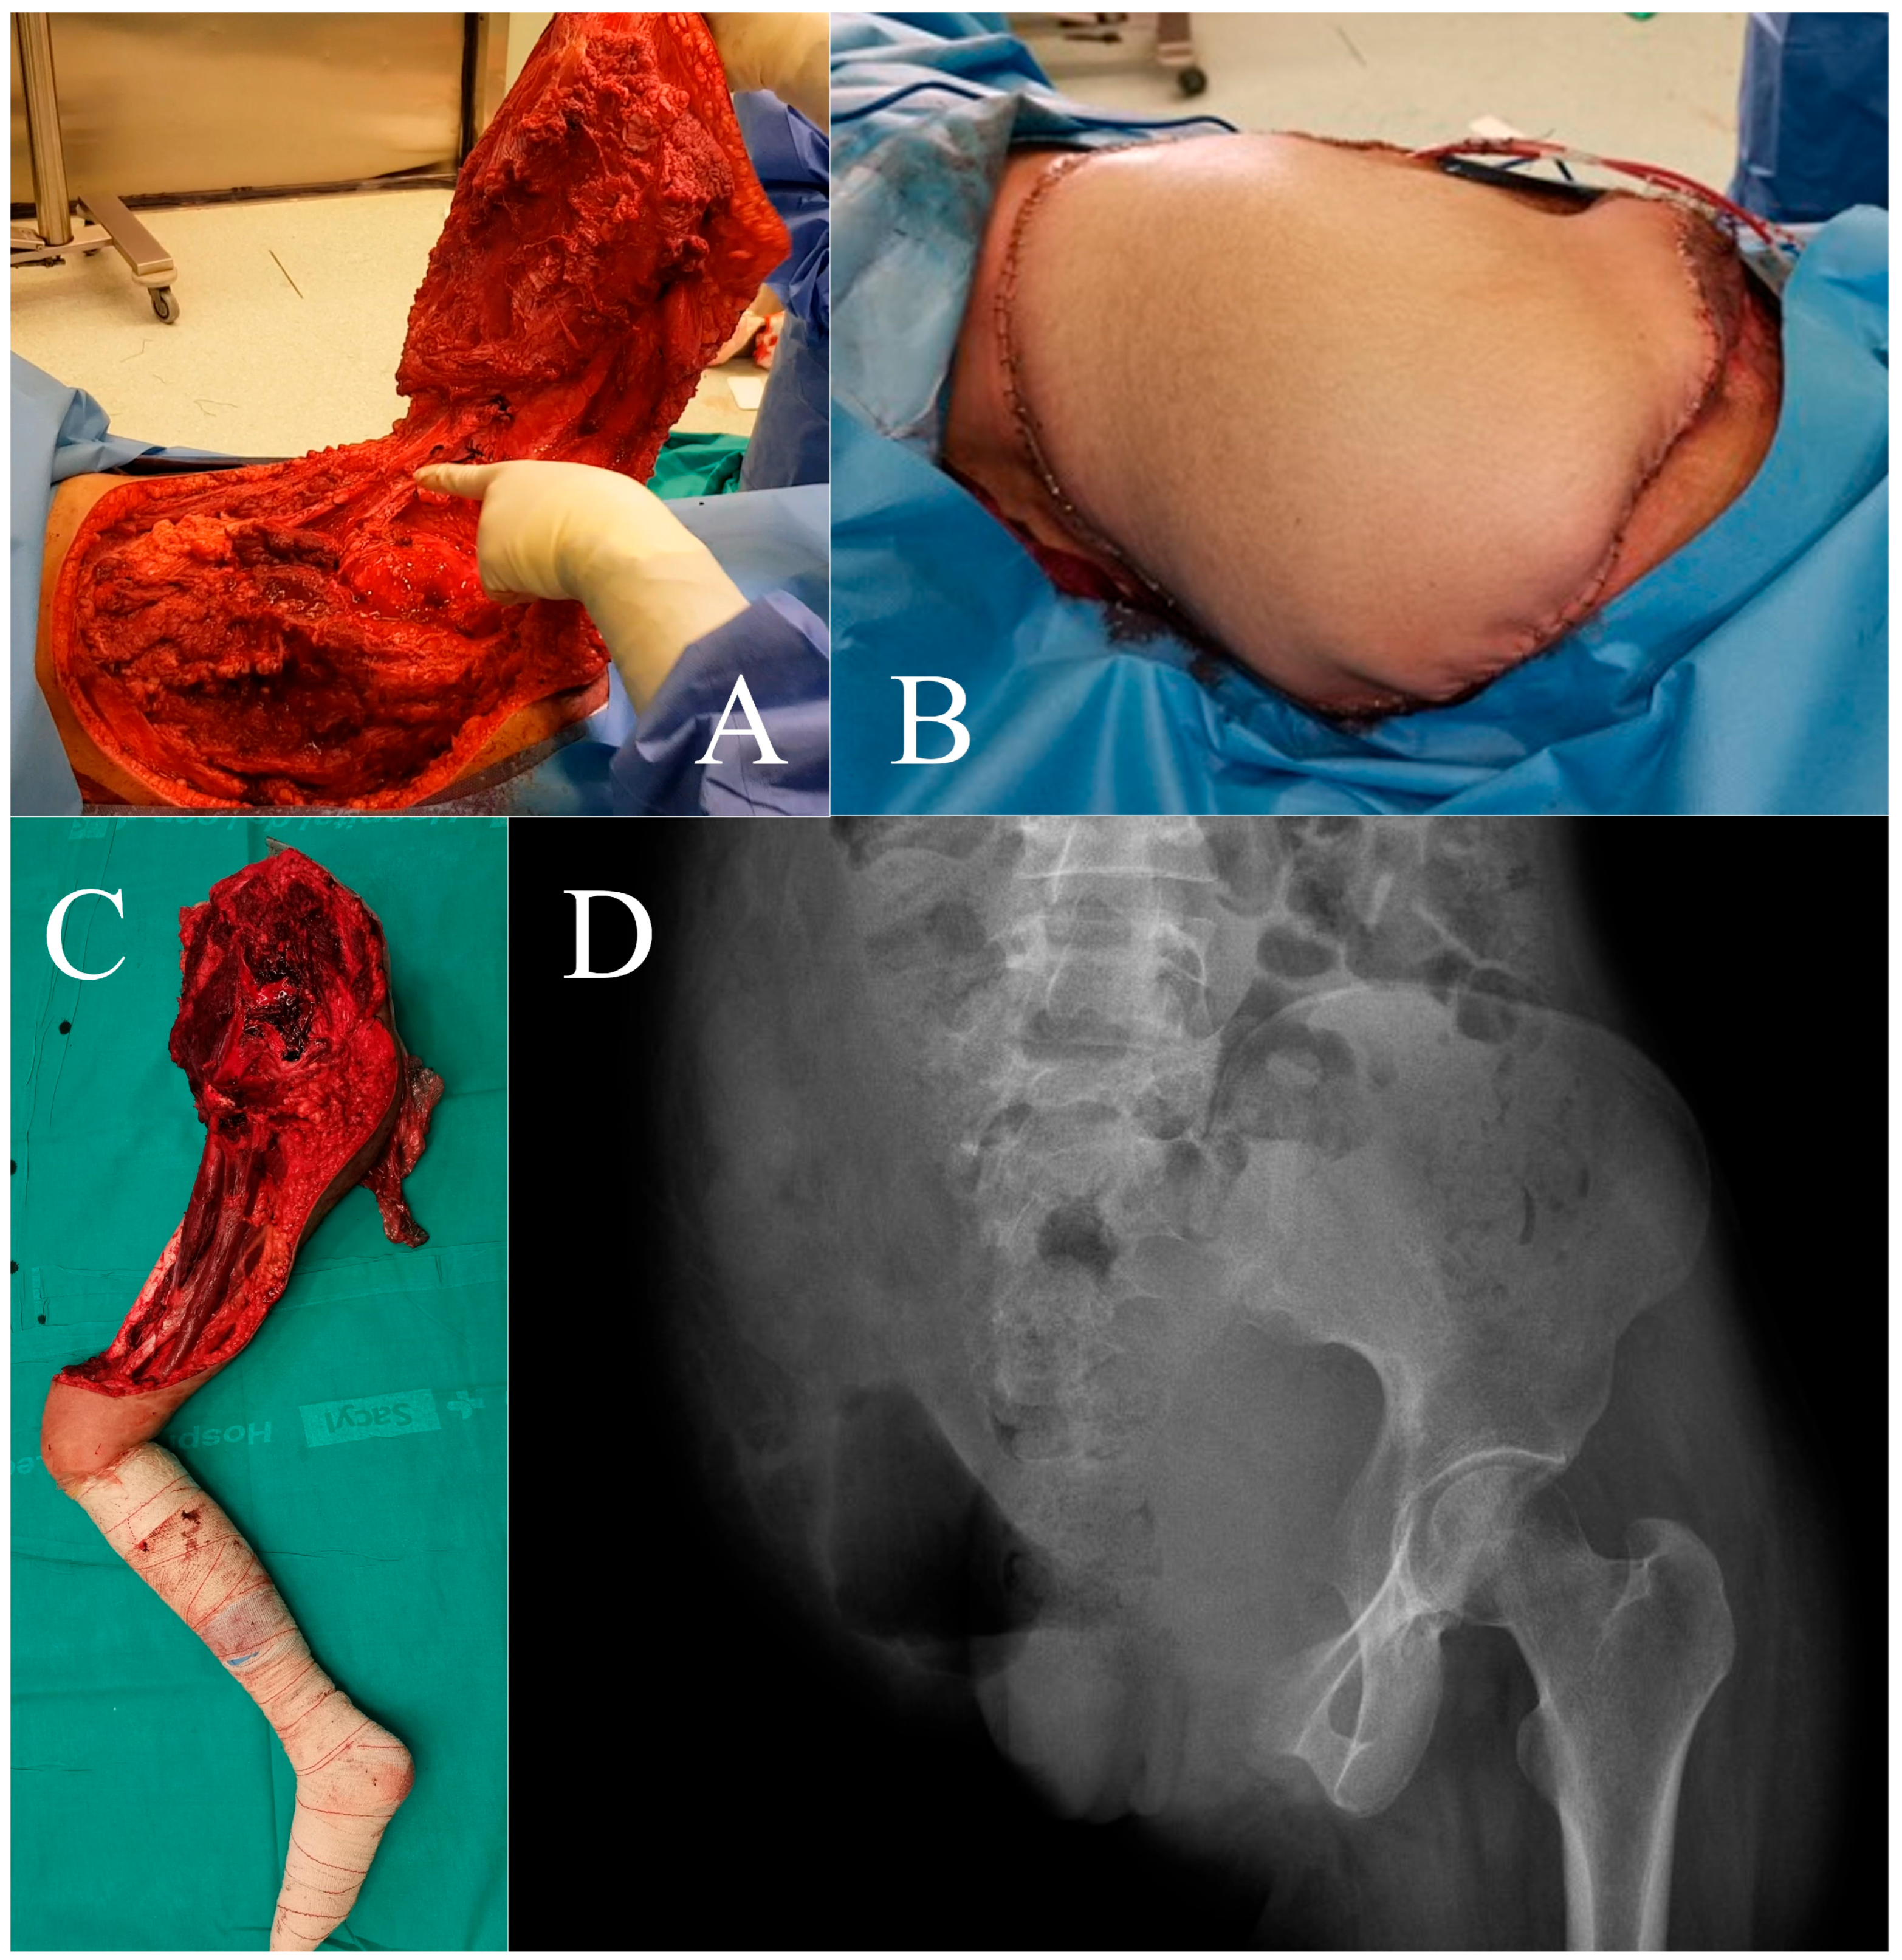

2.1. Case 1

2.2. Case 2

3.1. Case 1

3.2. Case 2